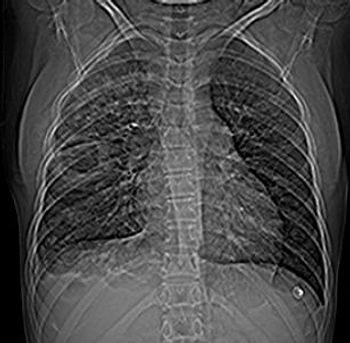

A 16-year-old female was referred for evaluation of fever of four days duration. The patient had a renal transplant done one week back and was found to be suffering from thrombosis of A.V. fistula in the upper extremity as per the history. The A.V.F thrombosis was confirmed by ultrasound examination. In addition patient had evidence thrombosis of the same upper limb.